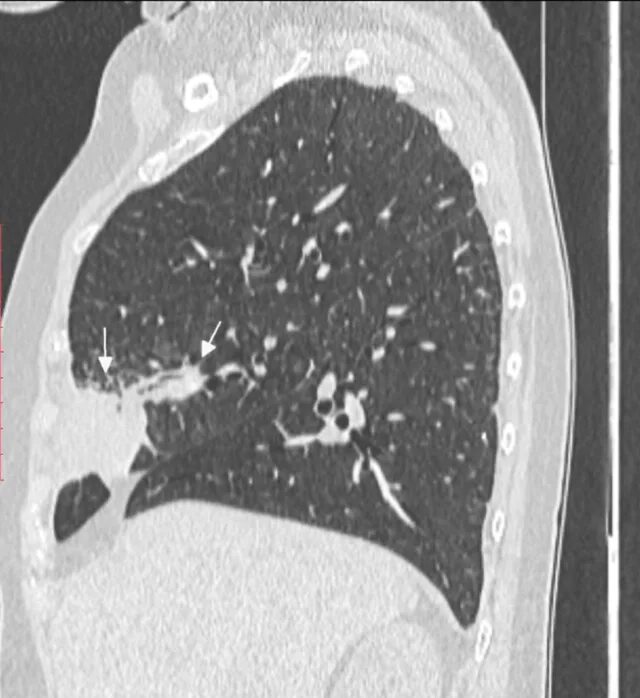

Как выглядит фиброз легких